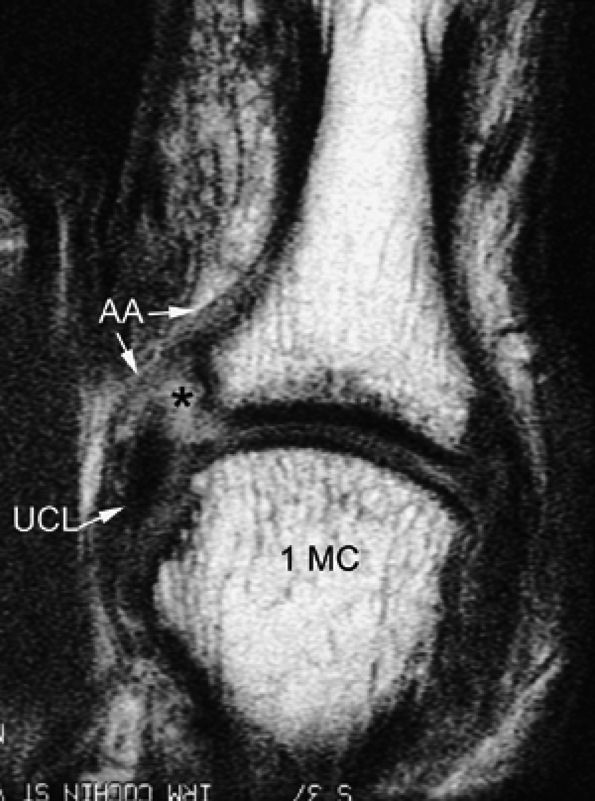

FIGURE 11.7 ● Coronal post-contrast T1-weighted image showing a nondisplaced tear of the UCL of the first metacarpophalangeal joint (MP) joint. The torn UCL is elongated beneath the adductor aponeurosis (AA). There is focal enhancement of the tear (asterisk). 1 MC, first metacarpal.

|